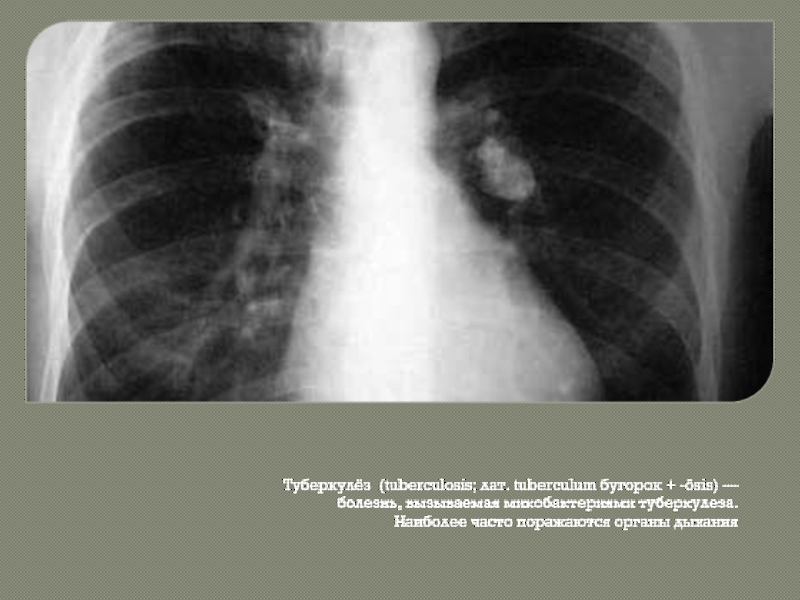

Симптомы туберкулеза: Как распознать и что делать

Раздел: Визуальные уроки